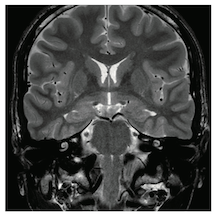

14-48 MR画像を以下に示す.描出されているものはどれか。3つ選べ。